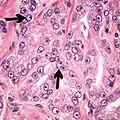

- Less specific findings.

- Mitoses (also seen in for example high-grade prostatic intraepithelial neoplasia (HGPIN) and prostate inflammation).[4]

- Prominent nucleoli[4]

- Intraluminal eosinophilic secretion[4]

- Intraluminal blue mucin[4]

Adenocarcinoma with two mitoses in reactive epithelium.